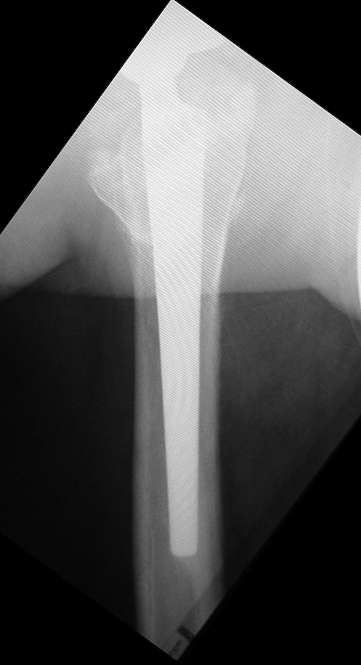

Здравствуйте уважаемые коллеги! Хочу попросить совета по следующему случаю.

Больной 1952 г.р. тотальное эндопротезирование обеих т/б суставов. Правый 2004г., левый в 2007г.

19.01.09. стали беспокоить боли в средней трети левого бедра по

наружной поверхности. Боли беспокоят только при ходьбе. Лежа и сидя

болей нет. Стоя вертикально, перенеся массу тела на правую ногу боль

исчезает, при равномерном распределении нагрузки снова появляется.

Снимки прилагаю.